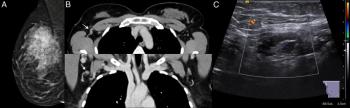

Researchers found the combination of magnetic resonance imaging (MRI) and contrast-enhanced mammography was nearly 22 percent more effective at detecting breast lesions than MRI-directed ultrasound.

The combination of magnetic resonance imaging (MRI) and computed tomography (CT) had a 63.83 percent sensitivity rate for tumor-infiltrated axillary lymph nodes in patients with breast cancer in comparison to a 36.11 percent sensitivity rate for the combination of mammography and sonography.